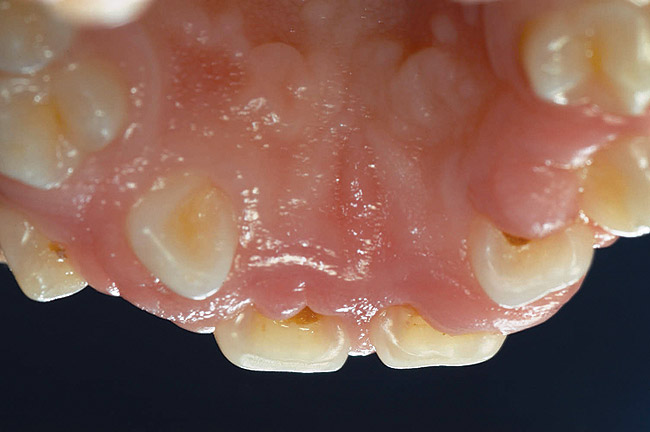

Finally, it must be noted that the psychological and emotional impact of gingival overgrowth receives no or little attention. As increasing numbers of pediatric patients are affected by systemic disease-associated gingival overgrowth, concern should be shown for how pediatric patients interpret what is happening to them and how affected children manage difficulties associated with facial appearance (Figure 1 through Figure 4).

Facial differences can bring stigma upon children and adolescents, affect their psychosocial development, self-esteem, and quality of life.35 Because of the centrality of the face, the mouth, and a smile in human interactions, the effect of gingival overgrowth on the smiles of thousands of children cannot be minimized. Regrettably, the media and public culture place a huge value on physical appearance, which can result in a lack of opportunity for and acceptance of those who look different.36 Reports of perception of physical appearance and social alienation suggest that children with facial differences undergo serious psychological and emotional problems as a result of the feelings of isolation and powerlessness.37 Because gingival overgrowth is a visible facial feature it can be categorized as a facial difference. Therefore, by extrapolation, the studies cited35-37 support that human relationships and interaction are negatively influenced by the appearance of gingival overgrowth. Life can be only the sum of moments, and moments lost to pain and suffering that are psychological or social in nature can mean as much or more than moments lost to physical pain and suffering.

Figure 3  Chronic gingival enlargement of unknown origin in an 8-year old girl. Frontal view.

Figure 3